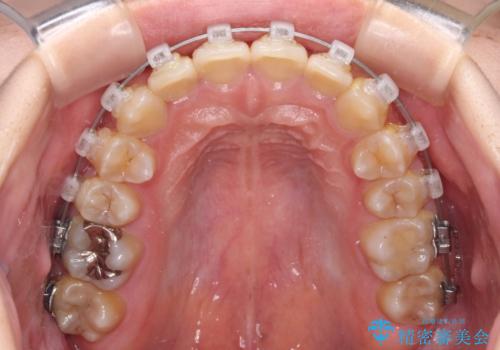

- 矯正装置

- クリアブラケット

- 犬歯のクロスバイトを気にして来院された患者様です。

マウスピース矯正とワイヤー矯正の両方を提案しましたが、インビザラインの自己管理が煩わしいとのことで、ワイヤー装置による矯正治療を行うこととしました。

犬歯は歯根が太くて長いため、クロスバイトを改善するのは大変であることが多いですが、比較的スムーズに改善することができました。

インビザラインであったら、もっと期間はかかっていたような印象です。